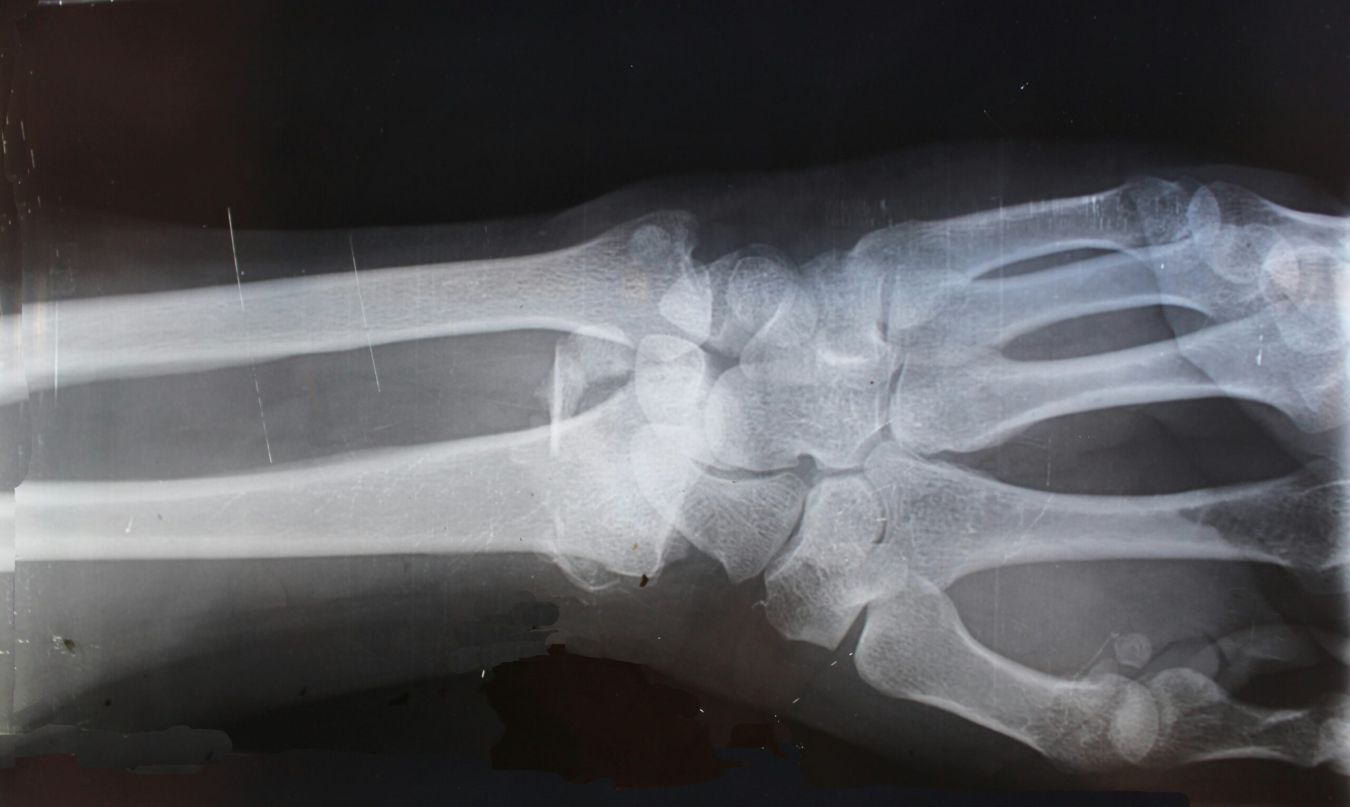

Huisartsen en huisartsenspoedpost sturen u in als zij denken dat er sprake is van een botbreuk. Gleamer wordt ingezet bij mogelijke breuken aan arm, van sleutelbeen tot en met de vingers (geen schouder) en van de knie tot en met de tenen, en soms ook bij andere breuken. De snelle beoordeling geldt voor alle patiënten die huisartsen of de huisartsenspoedpost op werkdagen van 8-21 uur insturen. Ook in het weekend biedt de afdeling radiologie deze service van 10-21 uur.

Na het maken van de röntgenfoto bij de afdeling radiologie in ons ziekenhuis, wordt de foto beoordeeld door Gleamer. Gleamer werkt snel en vrijwel foutloos. Voor extra zekerheid beoordeelt een radioloog de volgende werkdag de gemaakte foto’s voor een definitief oordeel. Als de radioloog iets anders ziet dan Gleamer, neemt hij binnen 24 uur contact op met de huisartsenspoedpost of de aanvragende huisarts.